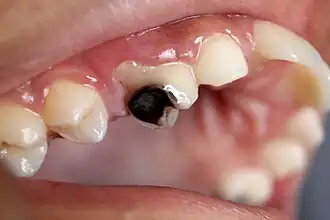

Early childhood caries

Photograph of teeth and gums on the lower right hand side of the mouth showing large caries lesions on all teeth at the level of the gum

Rampant caries caused by methamphetamine abuse